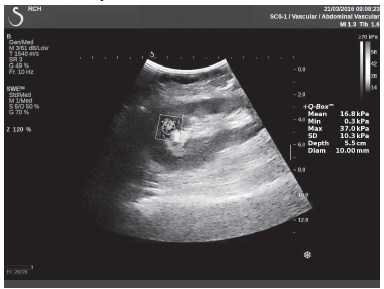

Клинический пример из первой группы. Пациент М., с хронической почечной недостаточностью. Трансплантация почки произведена от живого родственного донора. Трансплантат находится в правой подвздошной области. При нормальном функциональном состоянии трансплантата, показатели цветовой и спектральной допплерографии оценивались как удовлетворительные, с индексом резистентности не более 0,60 (рис. 1); показатели жесткости паренхимы почечного трансплантата при УЭСВ на различных участках составили от 20,05 до 29,18 кПа (рис. 2-4).

Рисунок 3. Исследование в режиме ультразвуковой эластографии сдвиговой волны у пациента М.: жесткость паренхимы в зоне верхнего полюса почечного трансплантата 21,4 кПа